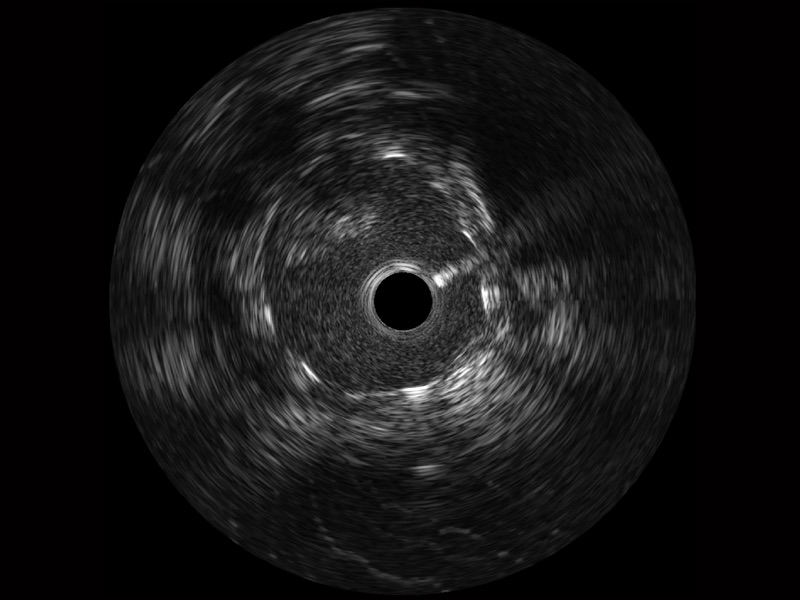

• 乐玩lewin国际宽频IVUS图像

• 传统IVUS图像

对比传统IVUS导管成像,乐玩lewin国际宽频IVUS图像的近场支架梁显影更细腻,远场中膜外血管仍清晰可辨,兼顾远中近,兼顾分辨力与穿透深度